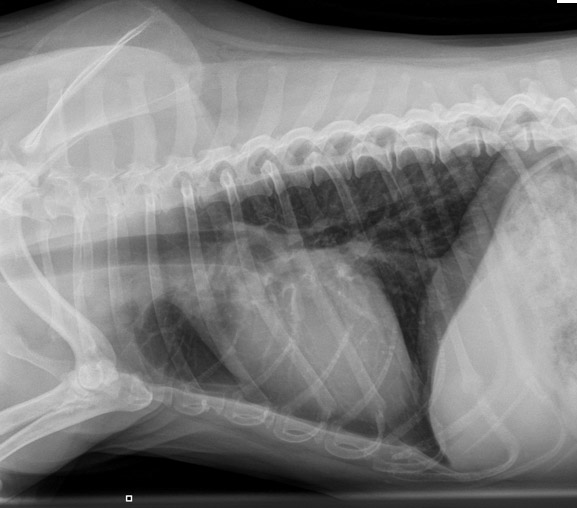

Вирусный бронхит у кошек - фото презентация